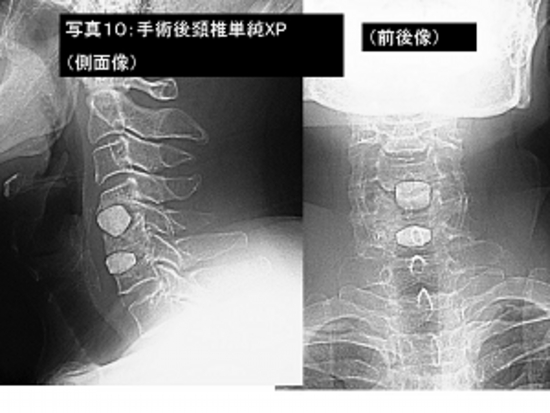

写真10:写真9の患者さんの手術後の頚椎単純レントゲン撮影像です。

写真11:頚椎骨折(交通事故)に対し前方固定術(チタンプレートを使用)を行いました。

手術後の頚椎CT検査です。チタンプレートを4本のねじでがっちりと固定しております。

患者さんは手術2週間後に歩いて自宅退院されました。